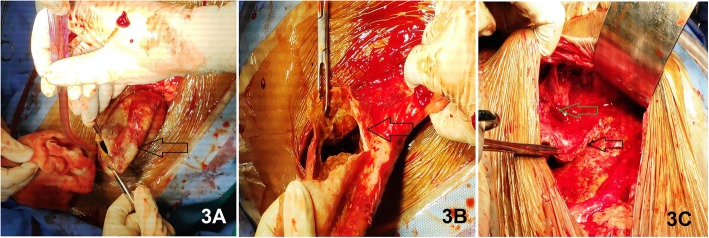

Fig. 3.

Intra-operative finding of a thick-walled (image 3A) cyst (Black arrows) containing purulent fluid and tissue debris (image 3B). Most of the cyst wall is free from surrounding tissues except (shown in image 3C) small portion over the inferior surface of the left liver lobe (Green arrow)